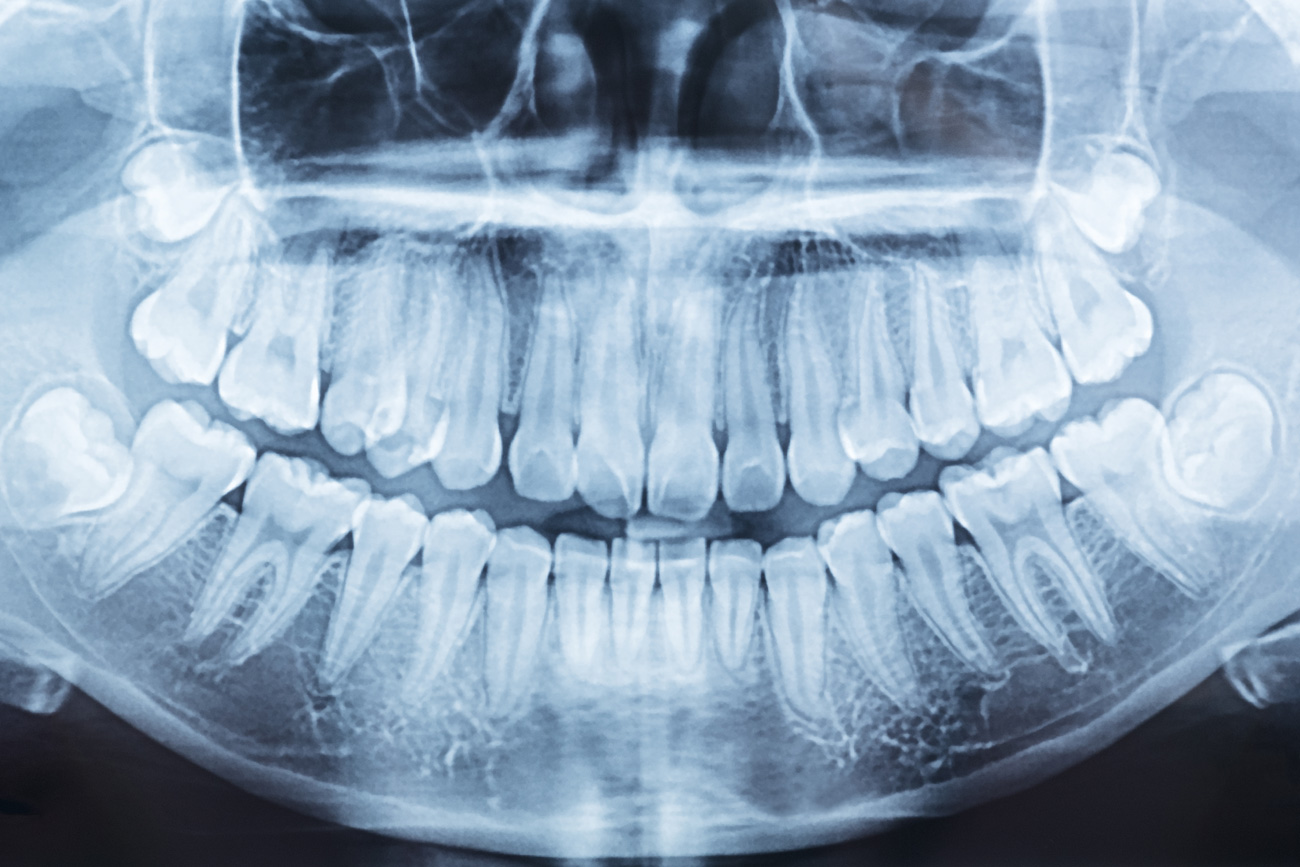

DSS use Carestream 8200 3D by Visualise 360 providing digital technology operating the “variable field of view” process which allows the dose of radiation to be considerably reduced. A proven and versatile CBCT system featuring an extended field of view that is ideal for practitioners who want to expand their treatment capabilities. Powered by premium imaging technologies and software, the CS 8200 3D delivers superb image quality in all modalities.

Versatile 2D/3D system ideal for expanding treatment capabilities

Extended field of view, up to

12cm x 10cm, best for full arch scans

Outstanding 2D/3D images thanks

to the latest premium technology

High-resolution 3D images

with limited artifacts and noise

State-of-the-art 2D/3D software

for easy image review